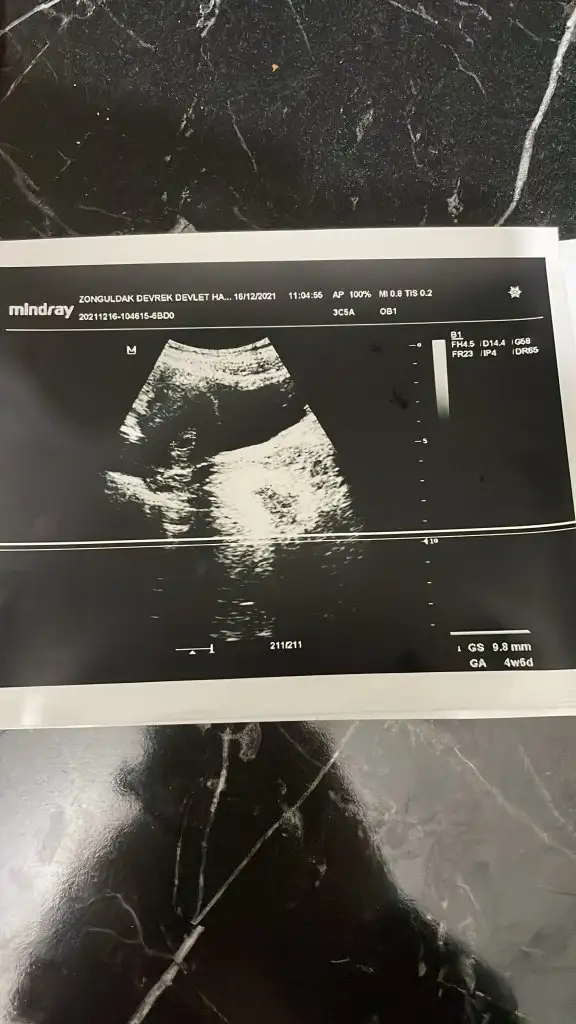

O Mm kesenin boyutudur. Henüz bebek bile oluşmamış olur bu haftada. 2 hafta sonra giderseniz daha net bilgiler elde edersinizmerhaba kızlar bende bir soru sormak istiyorum doktora gittim ultrasyon ile muayene etti iki ayrı ustrasyon kagıdı verdi birinde 4+5 9.1 mm birinde 4+6 9.8mm yazıyordu bu ne anlama geliyor kan degerinde 5355 cıkmıstı doktor bi acıklama yapmadı ikiz olma durumu varmıdır size nasıl kahıt vermişlerdi hatırlıyormusunuz